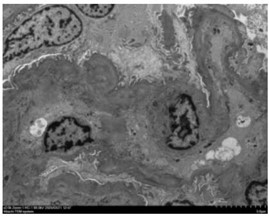

电镜描述:电镜下见1个肾小球。系膜细胞(0-3个/系膜区),系膜基质轻度增多。毛细血管内皮细胞节段增生、肿胀,腔内少量炎性细胞浸润。基底膜节段皱缩,未见明确分层及厚薄不均。系膜区、内皮下、基底膜内、上皮下均未见具有明确诊断意义的电子致密物沉积。足突节段融合并微绒毛化。